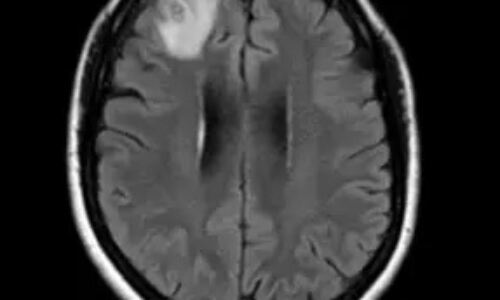

18일(현지시각) 뉴욕포스트는 휴가를 마치고 돌아온 여성 A씨가 뇌와 척수에 염증을 일으키는 기생충 감염병 '광동주혈선충증(angiostrongyliasis)'에 걸렸다고 보도했다.

처음엔 아무 진단을 받지 못했지만, 온몸이 타는 듯한 통증과 심한 두통으로 다시 응급실로 향했을 땐 미국 매사추세츠 종합병원 소속 카를로스 카스티요 박사에게 기생충 감염을 진단받았다.